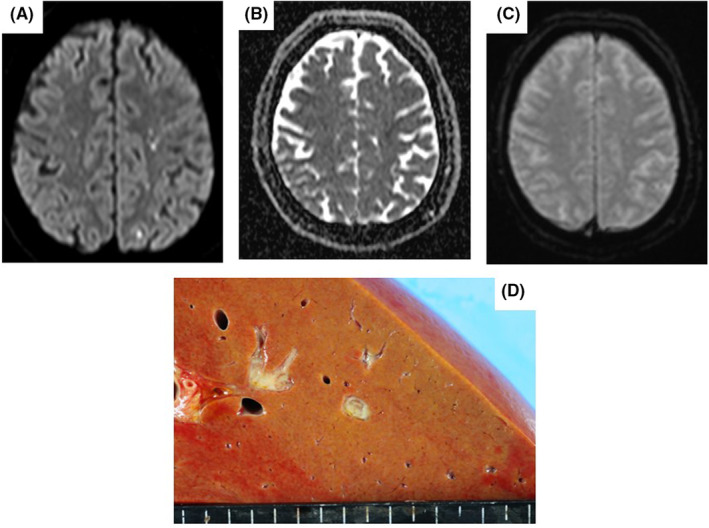

A 63‐year‐old man with diabetes mellitus, hypertension, and no history of neurosurgery was transferred to our facility with a 2‐day history of worsening consciousness disturbance, fever, and vomiting. Initial examination revealed a Glasgow Coma Scale (GCS) score of 3 (E1V1M1) with anisocoria; body temperature (BT), 36.7°C; pulse rate (PR), 150 beats/min; respiratory rate (RR), 40 breaths/min; blood pressure (BP), 109/73 mmHg; and oxygen saturation (SPO2), 100% on 10 L/min of oxygen via a reservoir mask. Laboratory results showed elevated inflammatory marker, creatinine, and liver enzyme levels; thrombocytopenia; and lactic acidosis. Computed tomography (CT) with contrast showed septic emboli in both lungs; otherwise, the infection focus was not observed. Diffusion‐weighted magnetic resonance imaging (DW‐MRI) showed disseminated hyperintensities in the brain, possibly due to infectious embolisms or micro‐abscesses. The observed pattern was consistent with embolic lesions (Figure 1A–C). Under the clinical diagnosis of septic shock complicated with pulmonary and CNS dissemination, fluid resuscitation, vasopressor support, steroid and antibiotic administration, and mechanical ventilation were initiated, and he was admitted to the intensive care unit (ICU).

(A–C) Magnetic resonance imaging scans in Case 1 showing multiple foci of restricted diffusion in the cortimomedullary junction. (A) The diffusion‐weighted image. (B) The apparent diffusion coefficient image. (C) The T1‐weighted image. (D) Autopsy investigation findings in Case 1 showing a small abscess in the liver.

Shortly after admission, his hemodynamic state deteriorated rapidly, leading to cardiac arrest, which required veno‐arterial extracorporeal membrane oxygenation for resuscitation. Despite aggressive treatment, the patient died 4 days after admission. Blood cultures indicated K. pneumoniae with a positive string test result. Autopsy revealed turbid cerebrospinal fluid and inflammatory cell infiltration in the spinal cord, consistent with bacterial meningitis. A liver abscess was also detected, which was not apparent on the initial CT scan (Figure 1D). Based on his clinical course and autopsy, the patient was diagnosed with K. pneumoniae sepsis with liver abscess and meningitis.

Magnetic resonance imaging is a useful method for differentiating consciousness disturbance. Bacterial meningitis can form subdural empyema, which may show as hyperintensity on DW‐MRI, as hypointensity on a restricted apparent diffusion coefficient, and as ring enhancement on T1‐weighted images. 12 , 13 In Case 1, brain images were consistent with infectious change.